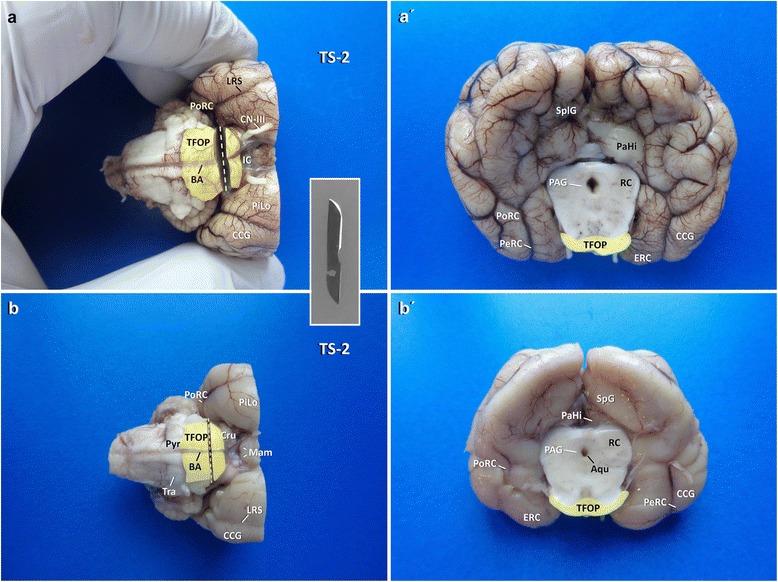

Fig. 6.

Planning of occipitotemporal brain dissection in three steps. TFOP: transverse fibres of pons; Aqu: mesencephalic aqueduct; PAG: periaqueductal gray matter. Canine brain

Procurement of the temporoventral body of the hippocampus

For the second section (TS-2; Fig. 3), the caudal part of the brain is approached ventrally. The transverse fibres of the pons (TFOP) are easily recognised in between the convergence of both crura cerebri (rostral) and the origin of the pyramis (caudal). A transverse section of the brain stem is performed with a pointed blade (e.g. scalpel blades no. 11 (cats) or 22 (dogs)), pointed ventrodorsally, just separating the rostral quarter of TFOP from its caudal three quarters (Fig. 5). That way, the caudal surface of the rostral mesencephalic stump ventrally reveals the TFOP, the dorsal border of which serves as the next landmark (Figs. 6 and 7).

Fig. 5.

Planning of TS-2 (a, b) and inspection of the occipitotemporal brain and mesencephalon (a′, b′) in dog (a′, a′) and cat (b, b′). Transection is performed by a tipped blade (inlet). Aqu: mesencephalic aqueduct; BA: basilar artery; CCG: caudal composite gyrus; CN-III: cranial nerve III; Cru: crura cerebri; IF: intercrural cistern; LRS: lateral rhinal sulcus; Mam: mammillary bodies; PAG: periaqueductal gray matter; ParaH: parahippocampal gyrus; PeRC: perirhinal cortex; PiLo: piriform lobe; PoRC: postrhinal cortex; Pyr: pyramis. RC: rostral colliculus; SplG: splenial gyrus; TFOP: transverse fibres of pons; Tra: trapezoid body